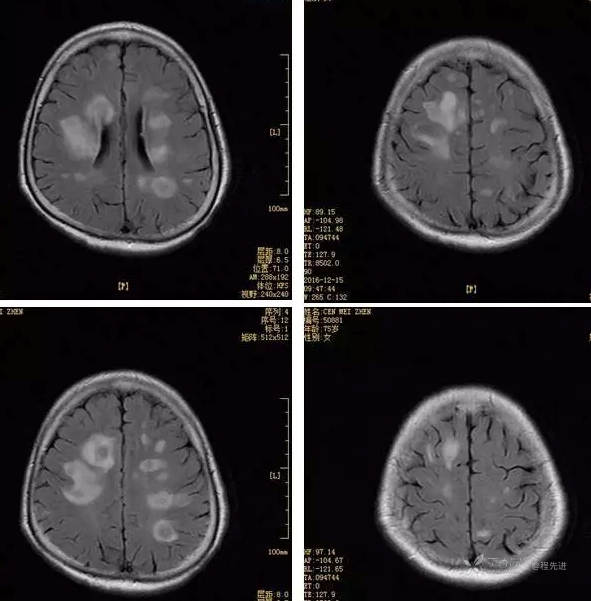

3月特别精彩病例|头晕伴左侧肢体乏力、行走不稳1周【结果已公布】

患者性别:女

患者年龄:75岁

简要病史:头晕伴左侧肢体乏力、行走不稳1周。否认高血压、脑梗塞、肝炎、糖尿病、肺结核病史。否认疫区疫水接触史。